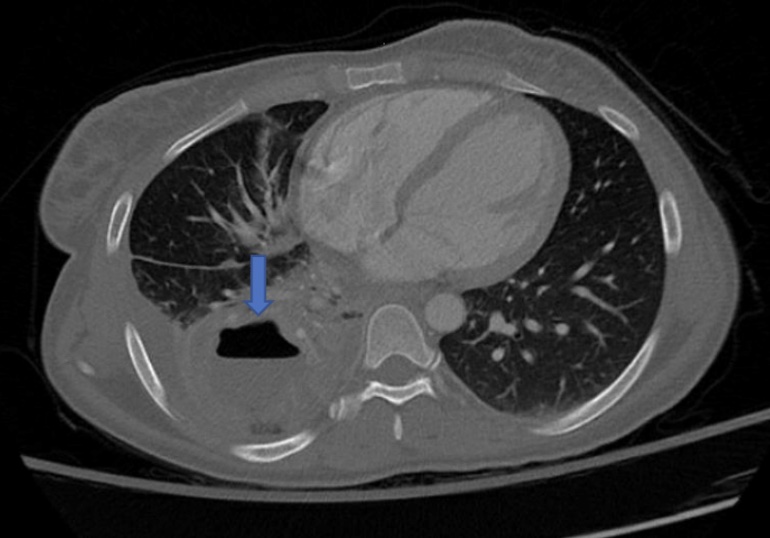

Or viewed on CT

Answer: Cavitary lesion with air-fluid level consistent with abscess from septic emboli secondary to infective endocarditis